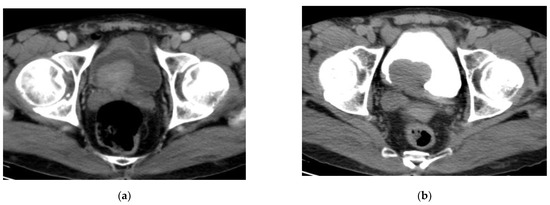

2.4. CT Urography

- T0:

- no evidence of tumor.

- Ta:

- noninvasive papillary carcinoma.

- Tis:

- Carcinoma in situ.

- T1:

- Tumor invades the subepithelial connective tissue (lamina propria).

- T2:

- Tumor invades the musclularis propria bladder wall